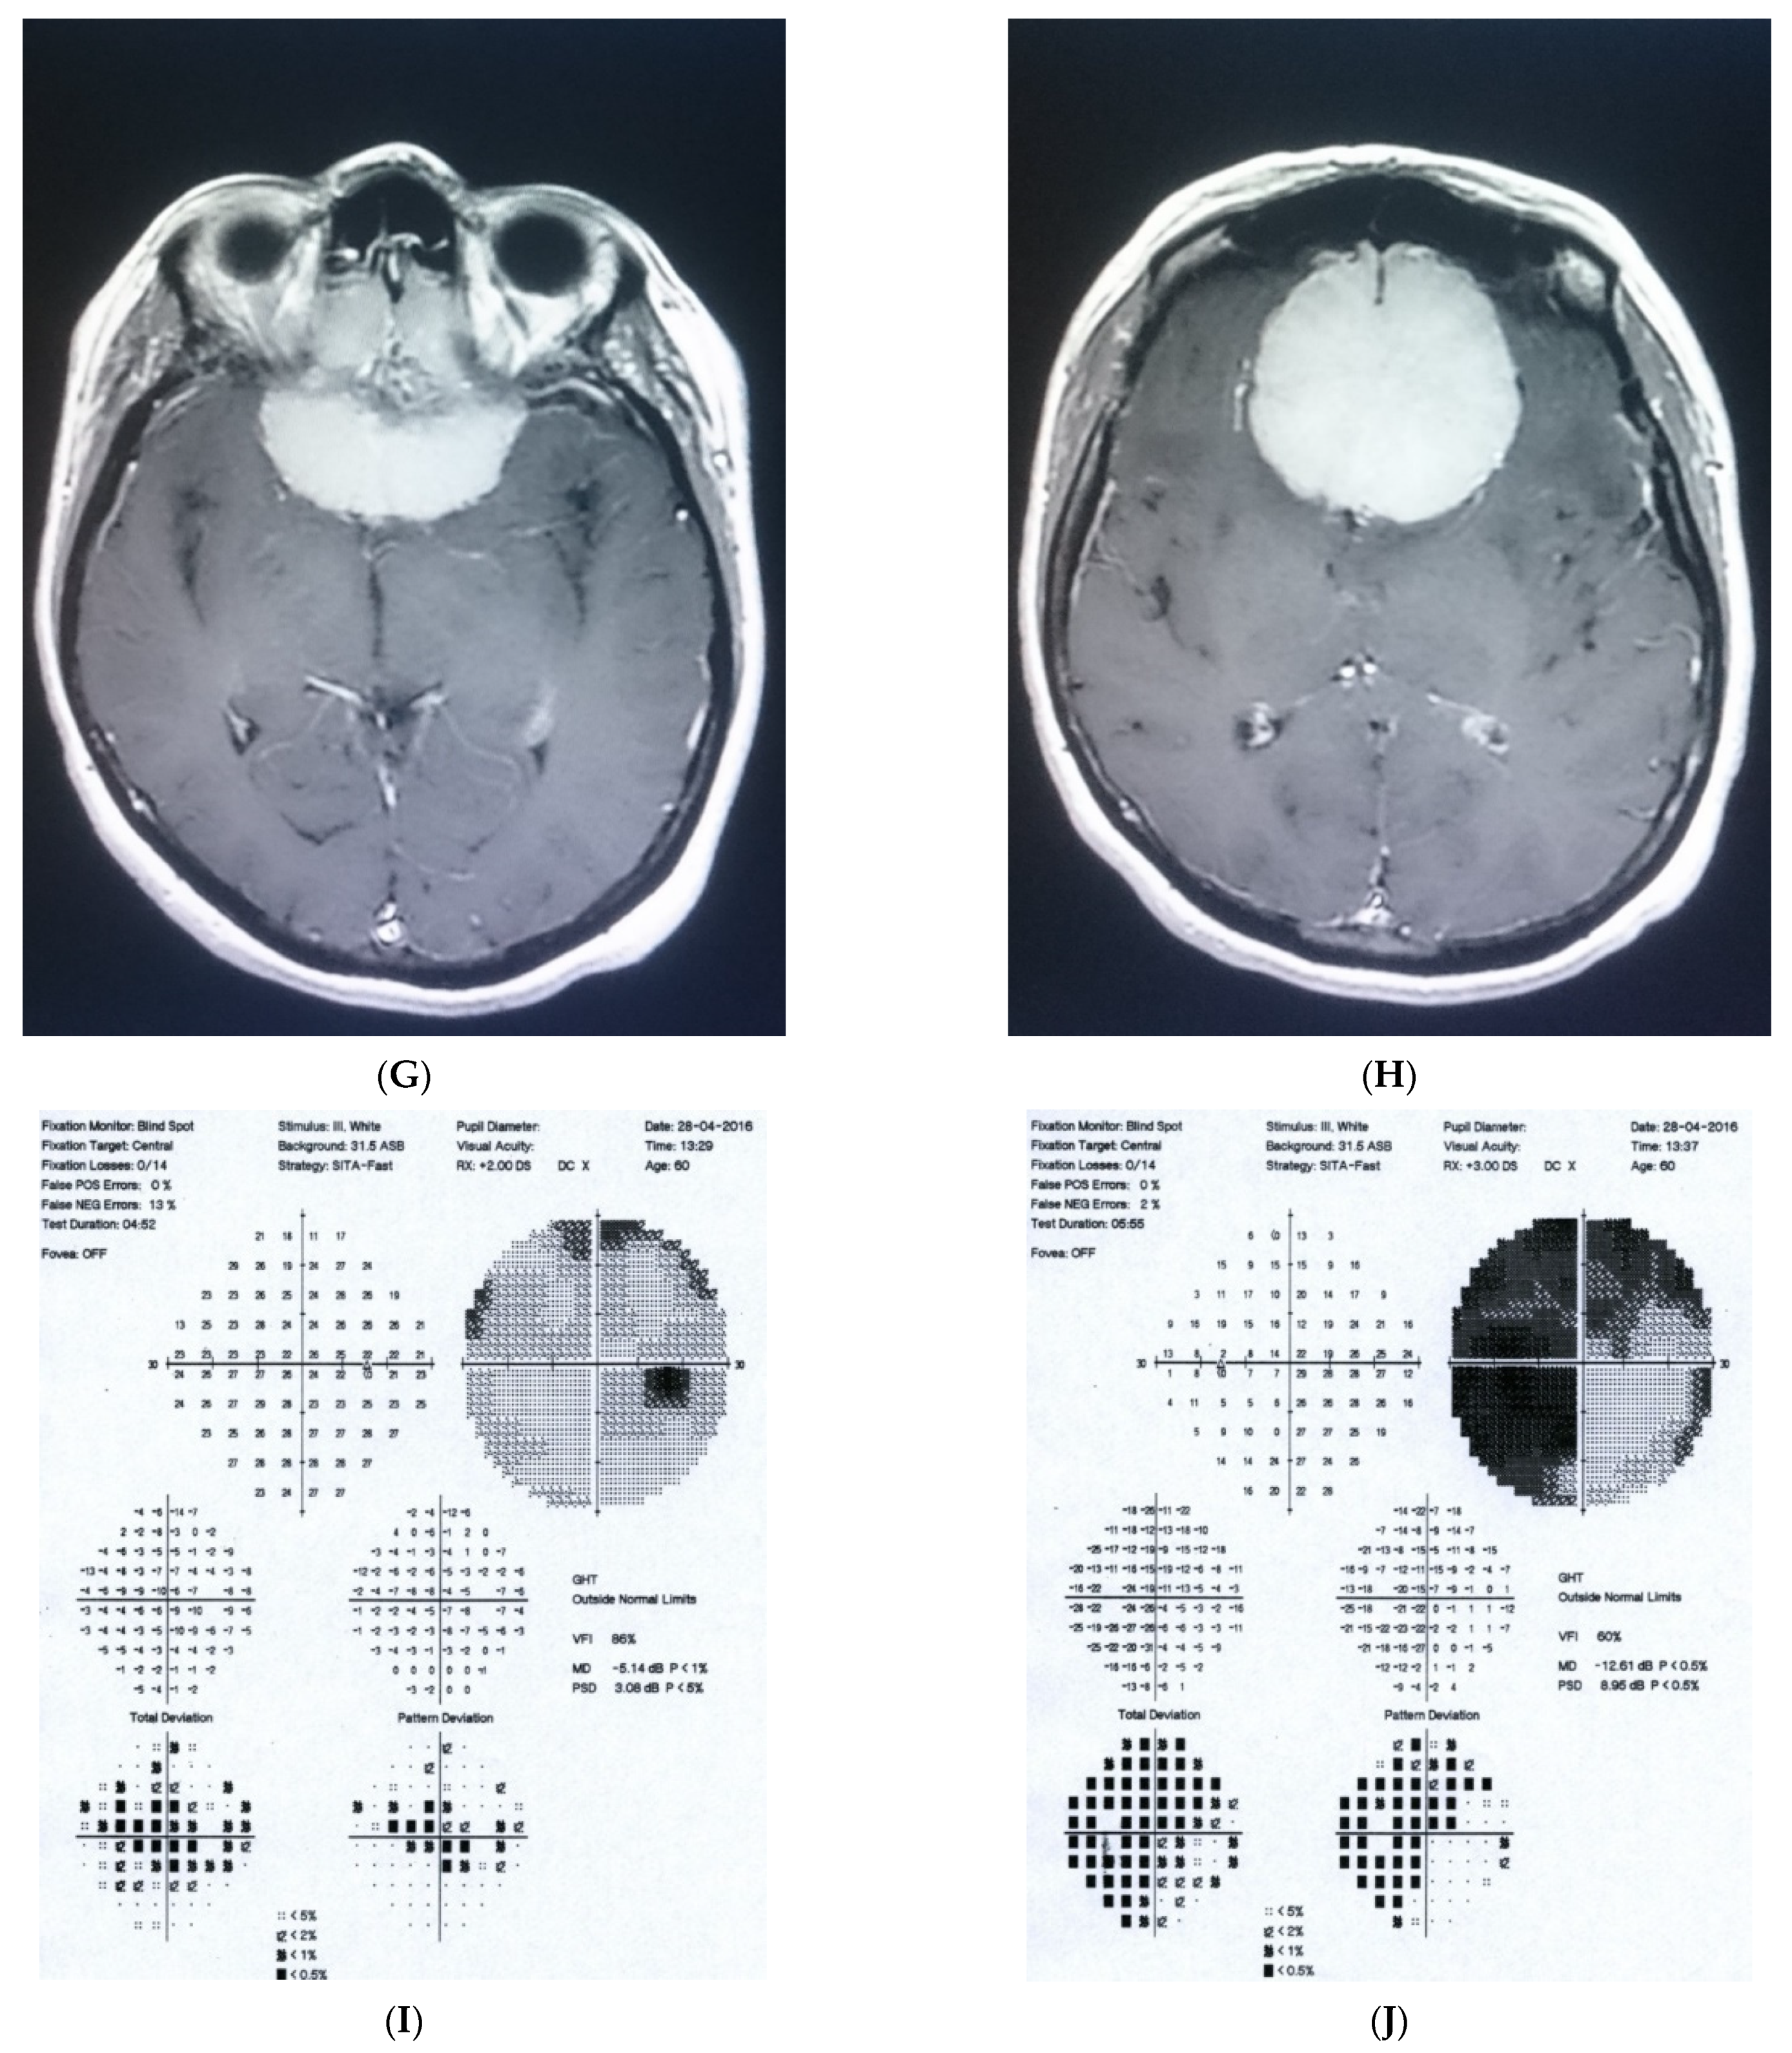

2.2. Case 2

2.3. Case 3

2.4. Case 4